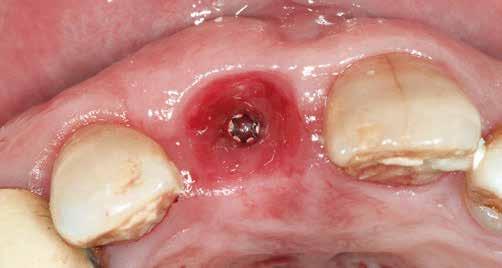

1. ábra: Műtét előtti fogászati panorámafelvétel, amelyen a hiányzó felső állcsont jobb első premolárisát és a szabad véggel rendelkező hidat láthatjuk. — 2. ábra: Az implantátum méreteinek megtervezése CBCT-vel. 3. ábra: Bukkális lágyrészdefektus. — 4. ábra: A biológiai szélesség értékelése a vertikális lágyszövetvastagság alapján. 5. ábra: Palatinális „tekercslebeny” – Palatal roll flap. — 6. ábra: Bredent medical copaSKY 4x10 implantátumbeültetés. 7. ábra: Szubkresztális implantátumbeültetés a várható biológiai szélességnek megfelelően.

8. ábra: Egyéni ínyformázó titánbázison, tulipán alakú emergenciaprofillal. — 9. a. ábra: A sebzárás okkluzális nézete.

(2. ábra). A lágyszövetek értékelése Seibert szerinti I. osztályú csontdefektust állapított meg (3. ábra), ezért a beavatkozáskor palatinális „tekercslebenyt” preparáltunk (palatal roll flap), és implantációt végeztünk, hogy kompenzálni tudjuk a bukkális lágyszövet-behúzódást. Megmértük a vertikális lágyszövetvastagságot, és úgy terveztük, hogy a szubkresztális implantátum beültetése összhangban legyen a biológiai szélesség kialakulásával a transzgingivális gyógyulási periódus alatt (4. ábra)

Sebészeti eljárás

Az eljárást helyi érzéstelenítés mellett végeztük (4%-os articaine-hidroklorid 1:100 000 adrenalinnal). Papillakímélő, U alakú palatális bemetszést végeztünk, teljes vastagságú nyálkahártyalebeny preparálás történt, a lebenyt bukkálisan feltekertük (5. ábra). A lebeny bukkálisan feltekert részén de-epitelizációt végeztük el, amellyel kompenzálni tudtuk a bukkális lágyszöveti defektust. Szakaszos előfúrást végeztünk, és a bredent copaSKY 4x10 implantátumot 30 Ncm behajtási nyomatékkal helyeztük be (6. ábra). Az implantátumot 1 mm-re szubkresztálisan helyeztük be, hogy később szélesebb emergenciaprofilt tudjunk kialakítani (7. ábra). Az egyedi ínyformázó úgy készült, hogy kompozitot vittünk fel a titánbázisra, és így formáztuk a lágyszöveteket a transzgingivális gyógyulási fázis során (8. ábra). Az egyéni ínyformázó tulipán formájú, hogy kialakítsa a kívánt emergenciaprofilt. A lágyszövetet feszülésmentesen zártuk #6/0 nem felszívódó, monofil fonallal (Optilene, B. Braun Deutschland; 9. a–b. ábra). Posztoperatív röntgenfelvétel készült, ami alapján az implantátum a szomszédos fogakkal párhuzamos elhelyezést mutatott (10. ábra). Posztoperatív utasításokat adtunk a páciensnek a műtéti terület körüli szájhigiénia fenntartása érdekében. A beavatkozást követő egy héttel a varratokat eltávolítottuk, és a kezelt terület kielégítő gyógyulást mutatott (11. ábra). A 4 hónap utáni késleltetett terhelést a páciens kívánsága szerint terveztük.